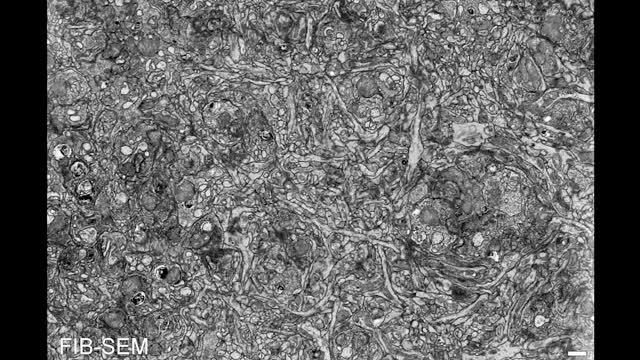

Image:

"Alarcon-Martinez, Villafranca-Baughman et al., CRCHUM" and Nature.

"Using a microscopy technique to visualize vascular changes in living mice, we showed that pericytes project very thin tubes, called inter-pericyte tunnelling nanotubes, to communicate with other pericytes located in distant capillaries," said Alarcon-Martinez. "Through these nanotubes, the pericytes can talk to each other to deliver blood where it is most needed."